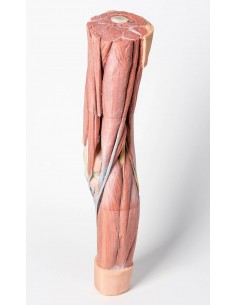

3D Anatomy 1.0 - Extremidades inferiores

Disección profunda del miembro inferior Erler Zimmer 3D anatomy Series MP1809